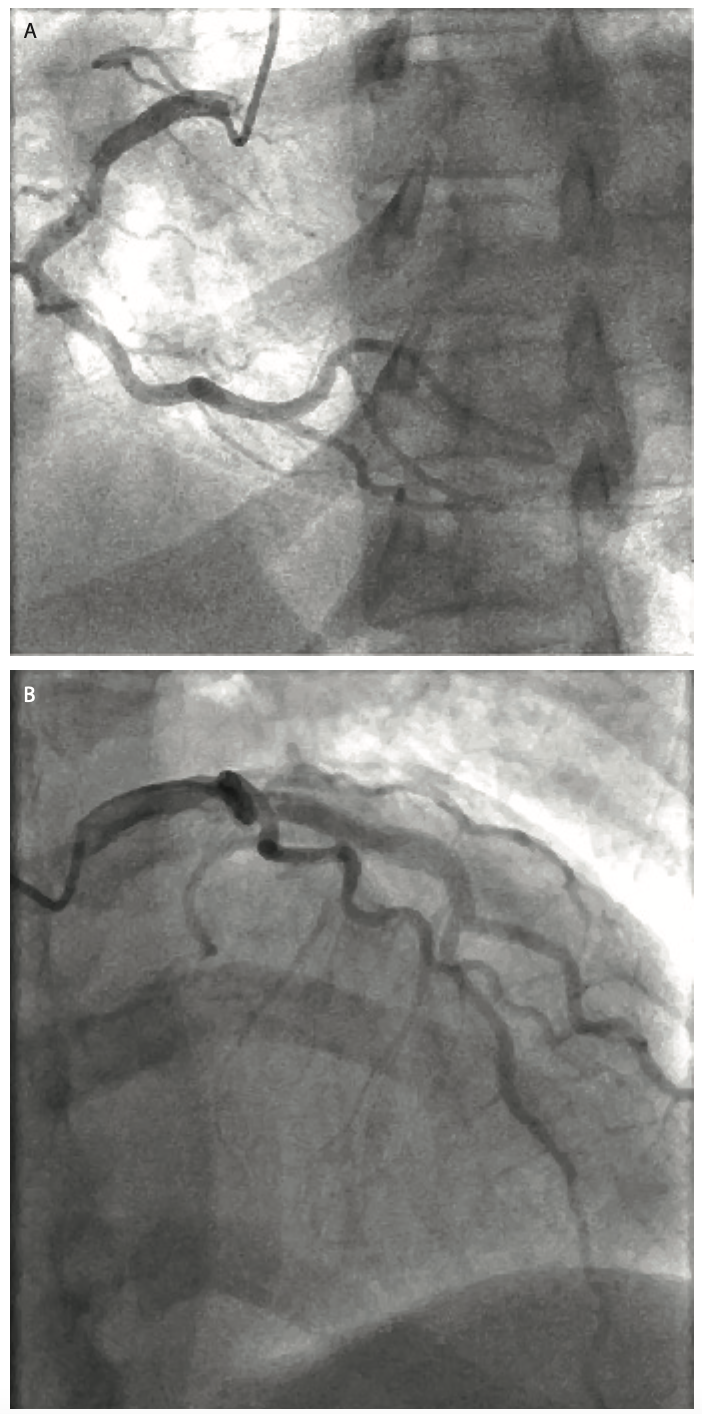

Right radial access was used, and despite difficulty selecting both right (RCA) and left (LCA) coronary arteries, the overall procedure time was 34 minutes with a total contrast dose delivered to the patient of 46.1 ml. The total contrast saved was 49.1 ml (51.5%). Ultimately, while the total contrast volume was 109.9% of the pre-determined threshold, both nephrology and interventional cardiology were pleased with the results. Without the contrast reduction system, total contrast volume delivered to the patient would have been 95.2 ml, or 6.8 times her eGFR. Image quality and our ability to assess the RCA (Figure 1) as well as the LCA (Figure 2) were maintained, despite significant contrast volume reduction.

The patient’s coronary arteries showed no CAD, and the patient was discharged home the same day after post-procedure hydration. A serum creatinine was obtained three days post procedure, showing no change from the pre-catheterization labs. No adverse events were reported, and the patient was recommended to continue her evaluation for her second renal transplant.